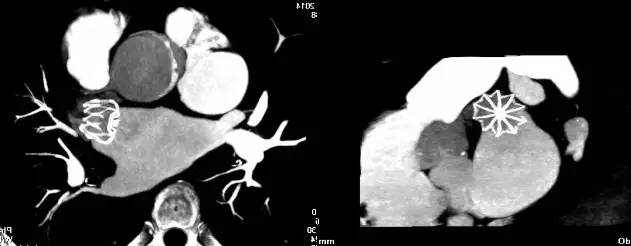

术后45天,因患者无法耐受TEE,行左房肺静脉CTA检查如(图5),未见封堵器表面血栓形成,封堵器形态良好,左心耳内血栓形成,封堵器与左心耳根部残余分流<5 mm(2.1 mm)。

图5